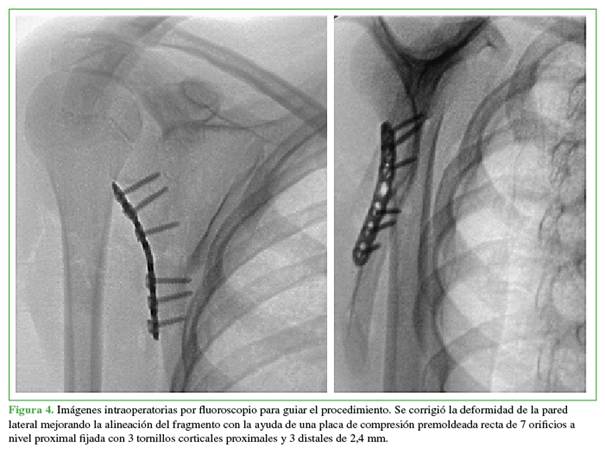

La alineación, la reducción y la ubicación del material de osteosíntesis se confirmaron con el intensificador de imágenes. Se logró una adecuada angulación de cada tornillo sin disposición intrarticular. Se cerró la herida por planos y se evaluó de inmediato la movilidad del hombro. Los arcos de movilidad pasiva y activa asistida habían mejorado considerablemente. La paciente continuó usando un cabestrillo hasta el control posoperatorio.

En las radiografías posoperatorias, se observó una alineación satisfactoria, con una reducción anatómica y posicionamiento del material de osteosíntesis. El cuerpo escapular fue reparado en su borde lateral, esto mejoró la estabilidad en el foco de fractura con la posición de la placa premoldeada. Se observó una mejor alineación gleno-humeral, logrando una restitución y un aumento del ángulo glenopolar, la corrección de la inclinación del segmento distal del foco de fractura y la alineación del cuerpo respecto a la radiografía lateral preoperatoria (Figura 5).